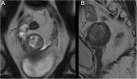

Endometrial cancer is the most common gynaecologic malignancy in developed countries and its incidence is increasing. First-level treatment, if no contraindicated, is based on surgery. Pre-operative imaging is needed for evaluation of local extent and detection of distant metastases in order to guide treatment planning. Radiological evaluation, based on transvaginal ultrasound, MR and CT, can make the difference in disease management, paying special attention to assessment of entity of myometrial invasion, cervical stromal extension, and assessment of lymph nodal involvement and distant metastases.